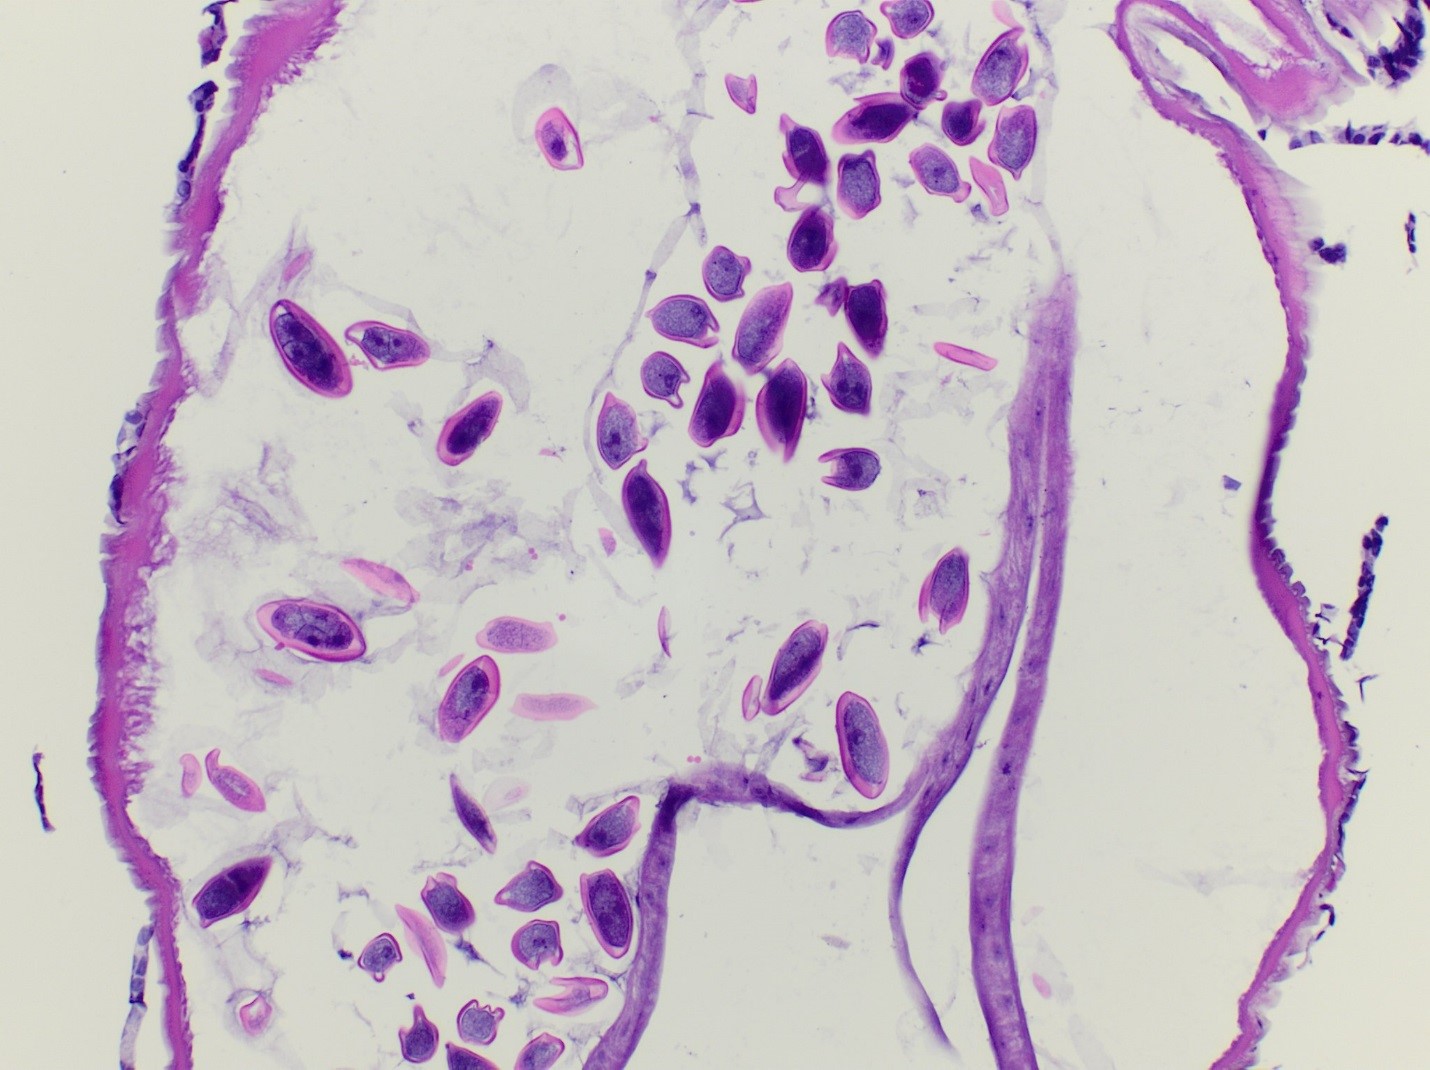

Gross examination of the appendectomy specimen showed an unremarkable appendix that measured 5.7 cm in length by 0.7 cm in diameter. There was no evidence of perforation. On sectioning, a small, white, “worm-like” structure (0.6 x 0.1 cm) was identified at the tip of the appendix and submitted for histologic examination. Microscopic review identified a female nematode with many eggs characteristic of Enterobius vermicularis. There was no acute inflammatory process identified upon microscopic review of the appendix.

Laboratory identification of E. vermicularis is usually made by using a piece of scotch tape or an adhesive paddle applied to the perianal skin in the morning and then visualizing the eggs microscopically. The eggs of pinworm are oval in shape & are flattened on one side with a thick capsule and measure between 50-60 x 20-30 um in size.On occasion, the eggs can be seen on pap smears as well. E. vermicularis worms can sometimes be visualized during colonoscopy, gastrointestinal & pelvic surgeries, and are capable of being identified by histology. Histologic sections of adult E. vermicularis worms usually show prominent lateral alae on the outer surface, testis or ovaries depending on the sex of the worm, and the intestinal tract. In gravid female worms, the characteristic eggs are numerous and can be helpful in the identification.